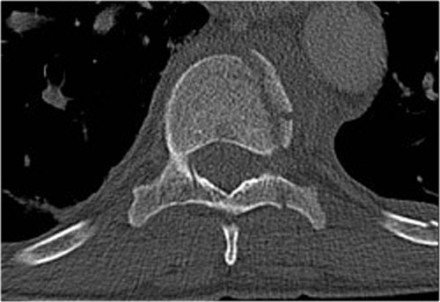

Case 4

Look at the images.

How would you describe the morphology and the PLC?

The findings are:

- Morphology: Distraction- 4 points

- PLC: always disrupted in distraction on posterior side - 3 points

- TLICS: 7 points